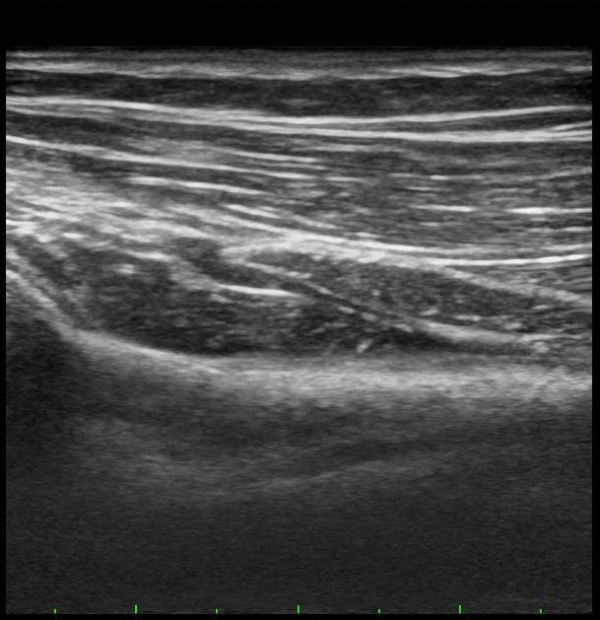

ŽÃËÀÚÀ» ¸»´ÜÀ¸·Î À̵¿ÇÏÀÚ Èİñ°£½Å°æÀÌ È¸¿Ü±Ù ±ÙÀ§ºÎ¿¡¼­ Àú¿¡ÄÚ ºÎÁ¾À» º¸ÀÓ(±×¸² 2).